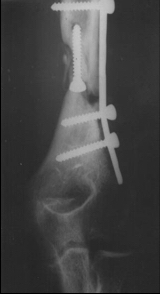

Humerus Psödoartrozlarının İlizarov

Yöntemi ile Tedavisi

Humerus bölgesinde İlizarov sirküler fiksatör uygulanmasın da dikkat edilmesi gereken hususlar:

2. Lecco kliniğinin geliştirdiği hibrid sistem en güvenli tespit metodudur. Buna göre suprakondiler bölgede uygulanan 2 adet stoplu K –teli dışında bütün tespitte lateral ve antero lateralden uygulanan Schanz vidaları kullanılmaktadır.

3. Paley ve arkadaşları distal humerusda her iki kondilden çapraz yollanan 2 adet Schanz vidasını stabil bir tespit olarak belirtmektedir. Klinik uygulamalarımıza göre medialden Schanz vidası tespiti yapılmadan ulnar sinir eksplorasyonu kanımca en güvenli yoldur.